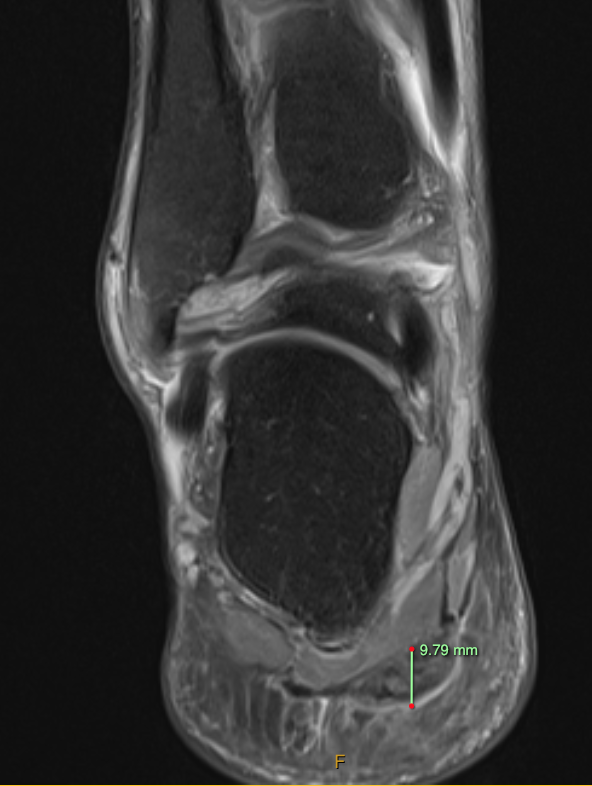

😲Severe fat atrophy after greater trochanteric pain injection using 80mg Triamcinolone Acetonide!! ⚠️Pre injection risk discussed ⚠️ Consider more soluble steroid ⚠️Is the needle long enough? ⚠️Ultrasound guided if available? Full paper 🔗 hjdbulletin.org/files/archive/…